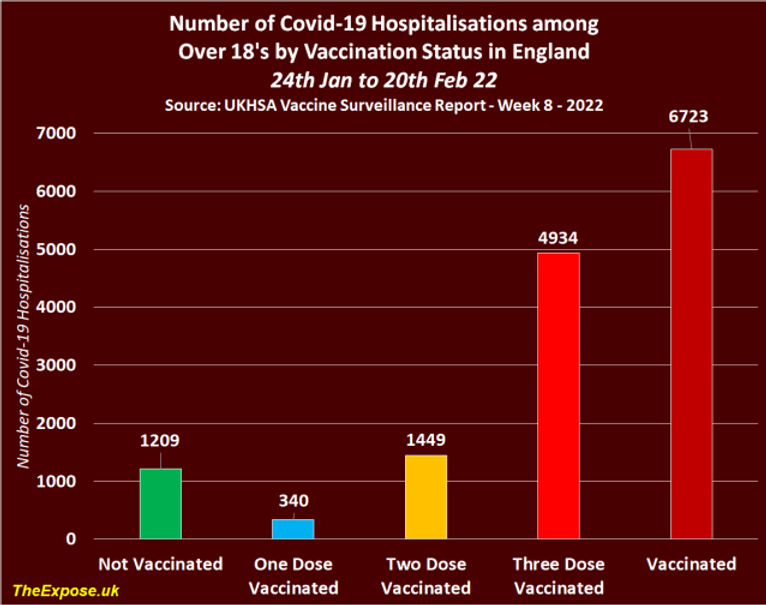

Table 11, found on page 42 of the latest report shows the number of Covid-19 hospitalizations by vaccination status in England between the 24th of January and the 20th of February, 2022, confirms the vast majority were again recorded among the triple vaccinated population.

Source – https://assets.publishing.service.gov.uk/government/uploads/system/uploads/attachment_data/file/1057599/Vaccine_surveillance_report_-_week-8.pdf

In all, there were 9,230 Covid-19 hospitalizations in England between the 24th of January and the 20th of February, 2022, and the triple vaccinated population accounted for 4,936 of them, whilst the nonvaccinated population accounted for 2,341 of them, 1,132 of which were allegedly children.

When we include children in the hospitalization figures we find that the vaccinated population accounted for 75% of all Covid-19 hospitalizations between the 24th of January and the 20th of February, 2022. But when we remove children, we find that the vaccinated population accounted for 85% of all Covid-19 hospitalizations among over 18’s in England.